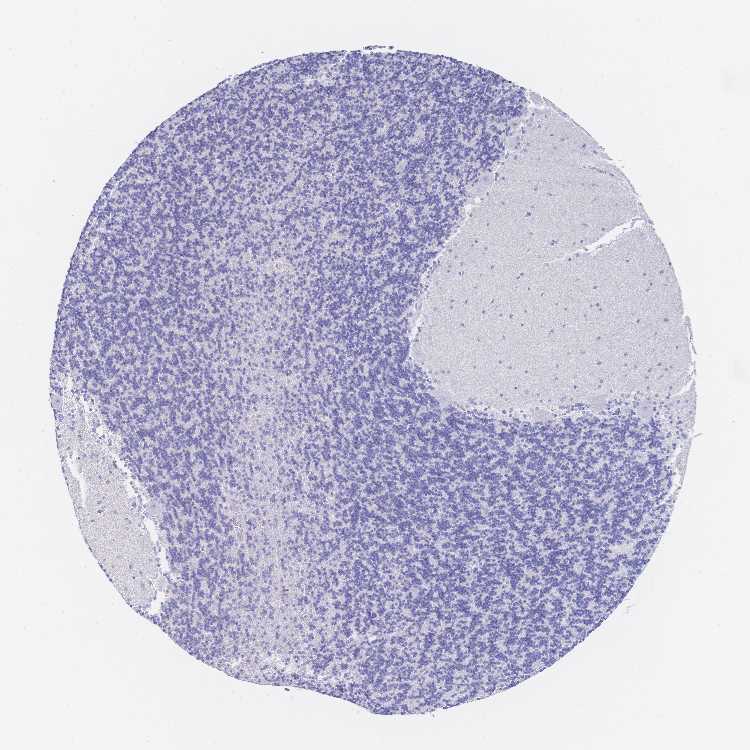

CEREBELLUM - Antibody stainingi

Antibody staining in the annotated cell types in the current human tissue is reported as not detected, low, medium, or high, based on conventional immunohistochemistry profiling in selected tissues. This score is based on the combination of the staining intensity and fraction of stained cells.

Each image is clickable and will lead to virtual microscopy that enables deeper exploration of all samples and also displays staining intensity scores, fraction scores and subcellular localization as well as patient and tissue information for each sample.

Antibody HPA057265Antibody HPA064297Antibody CAB022093

Purkinje cells Not detectedLowNot detected

Cells in granular layer Not detectedLowNot detected

Cells in molecular layer Not detectedMediumNot detected